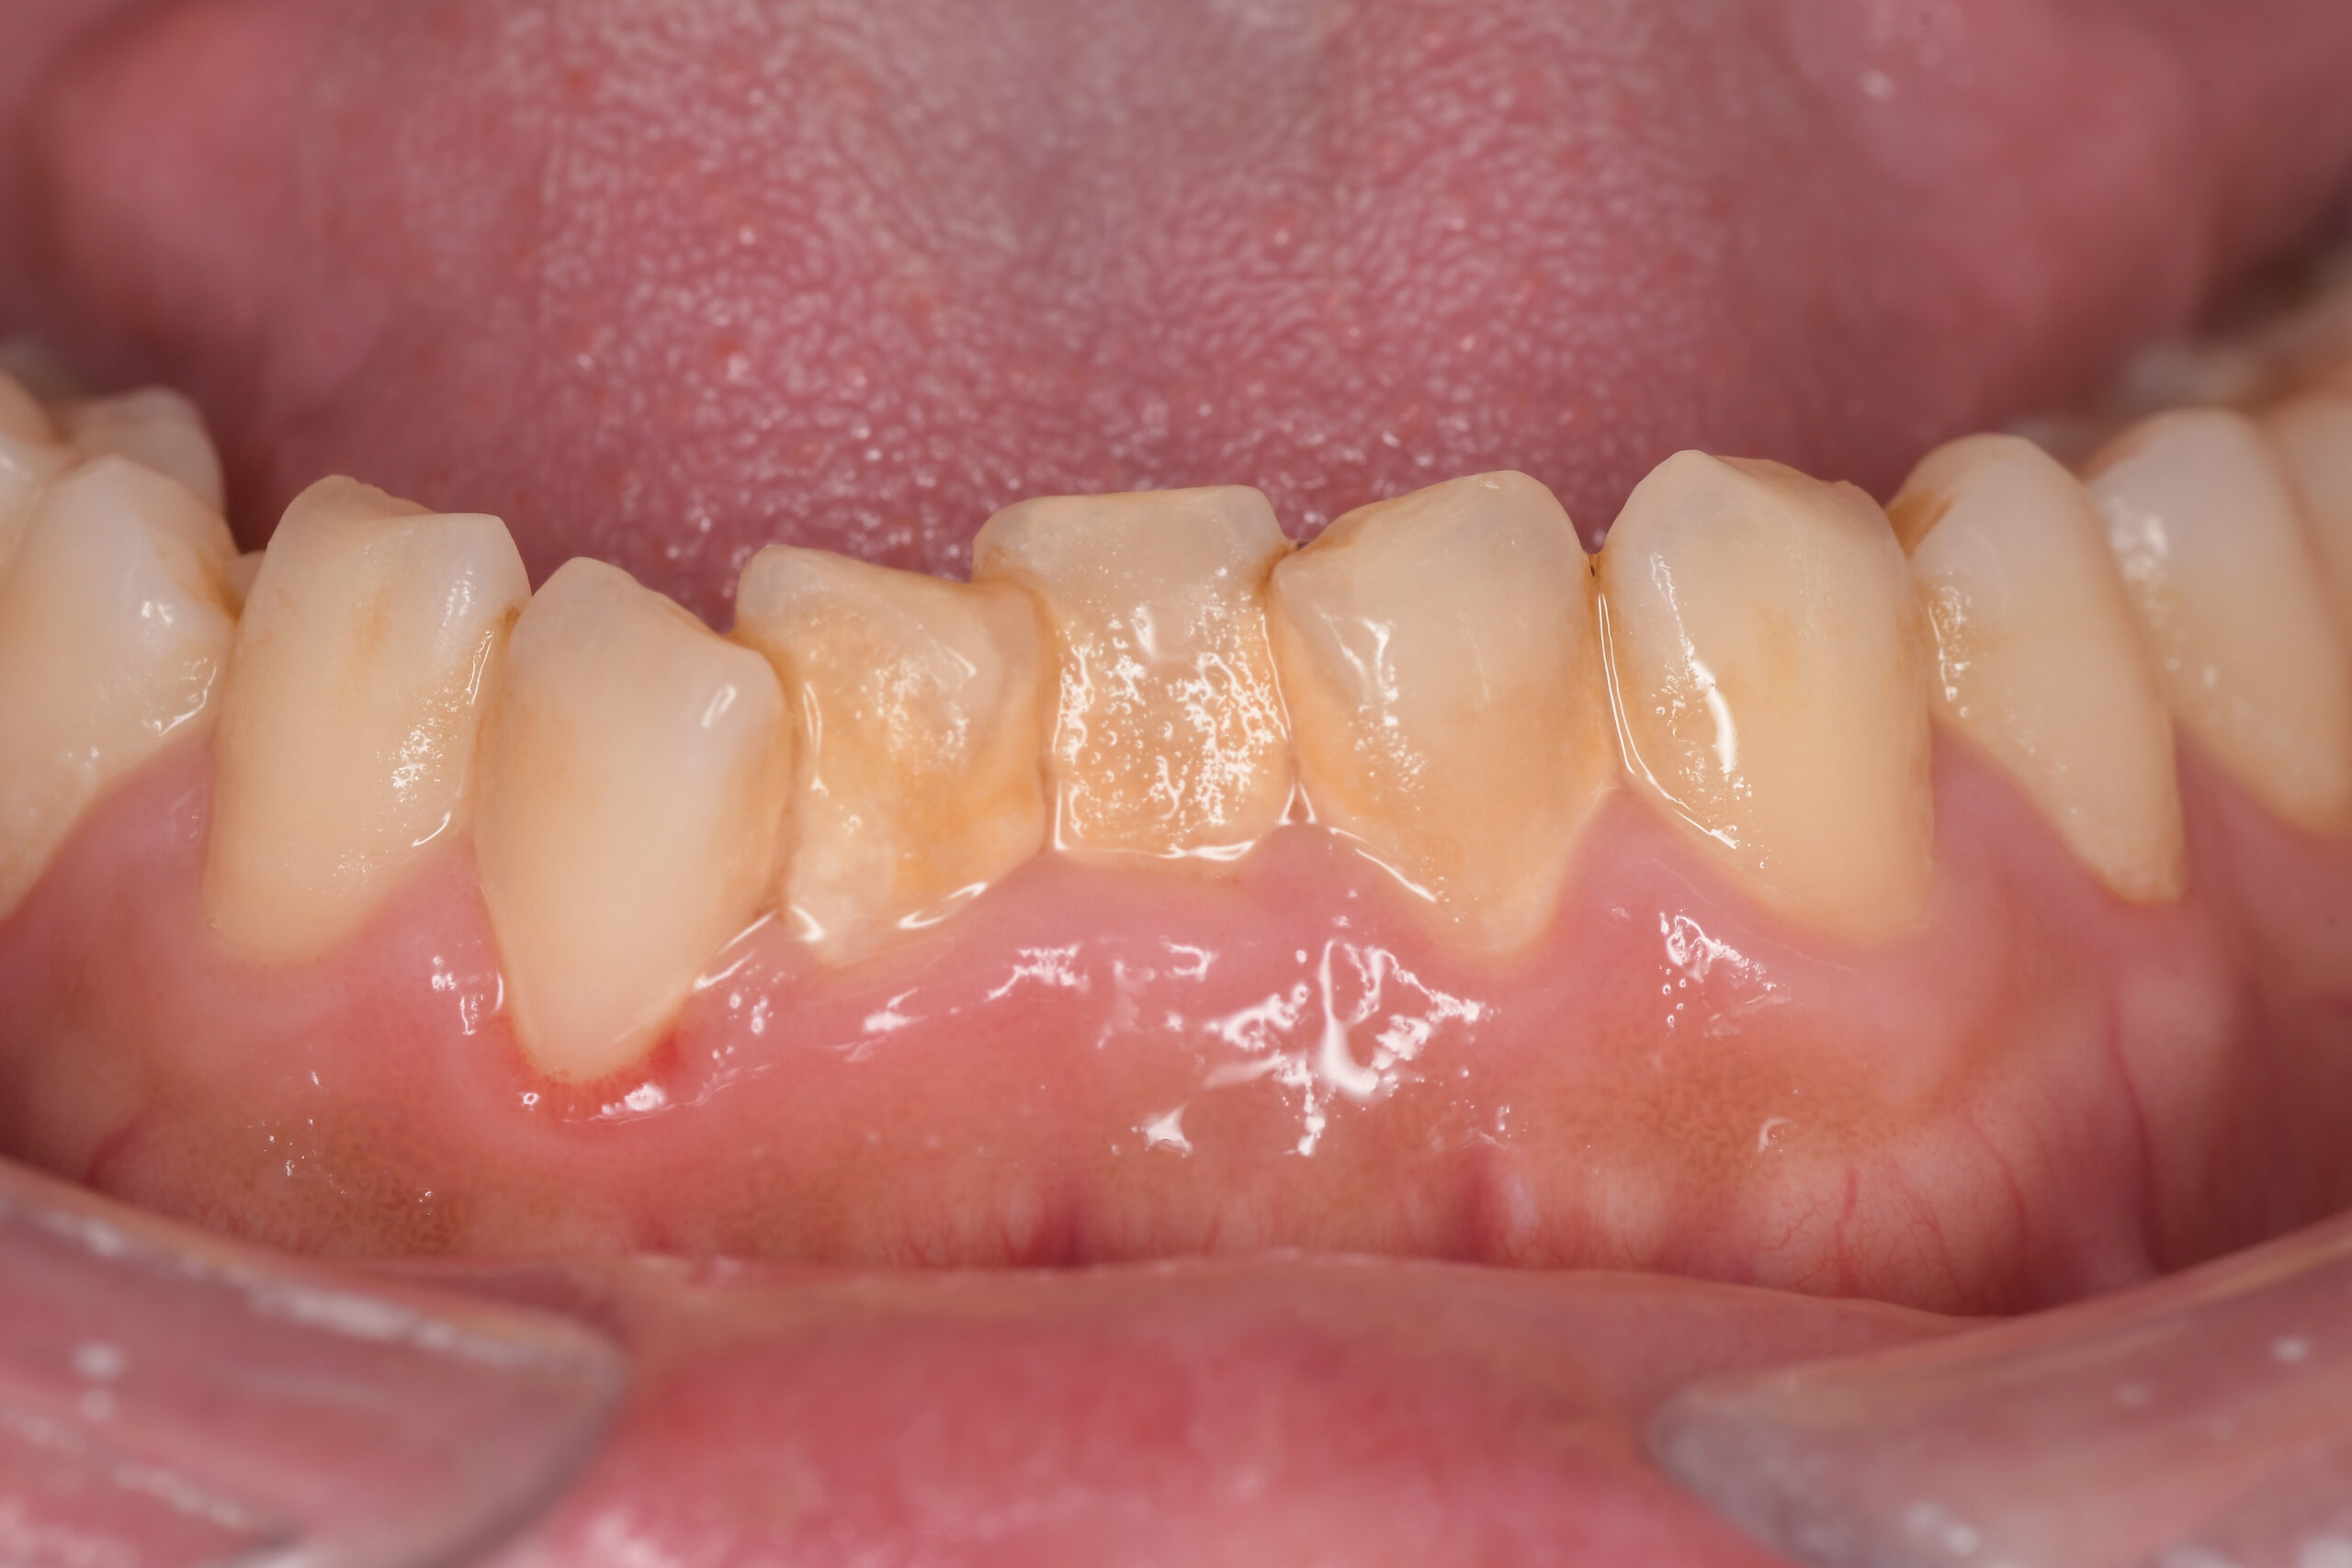

下顎before

下顎after

| 年齢・性別 | 27歳・男性 |

|---|---|

| 主訴 | 歯石とりたい |

| 治療内容 | スケーリング |

| 治療期間 | 30分 |

| 治療費 | 約1,500円(保険診療) |

| リスク・副作用 | 知覚過敏、歯肉退縮、出血 |

| 治療方針 | 歯列不正でプラークがつきやすいため、TBIを行い定期的に歯石を除去していきます。 プラークコントロールが出来るようになったら定期検診でクリーニングを行っていきます。 |